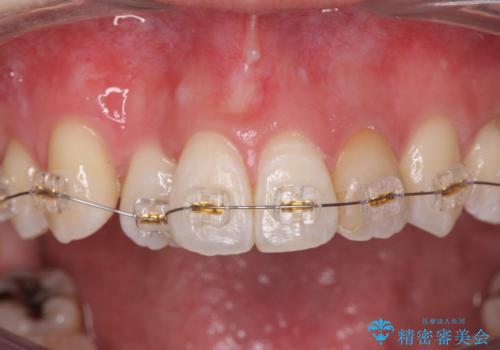

引っ込んだ前歯を並べたい マウスピースと部分ワイヤーのコンビネーション矯正

- インビザライン +部分ワイヤー矯正

まずマウスピース矯正インビザラインシステムで、引っ込んだ歯が並ぶためのスペースを作ったのち、部分ワイヤー矯正を行い短期間での配列を計画します。

マウスピース・ワイヤーそれぞれの長所をうまく活かすことで治療期間の短縮が可能となります。

このように前歯の部分ワイヤーは引っ込んでしまった前歯や がたつきを素早く改善することができます。